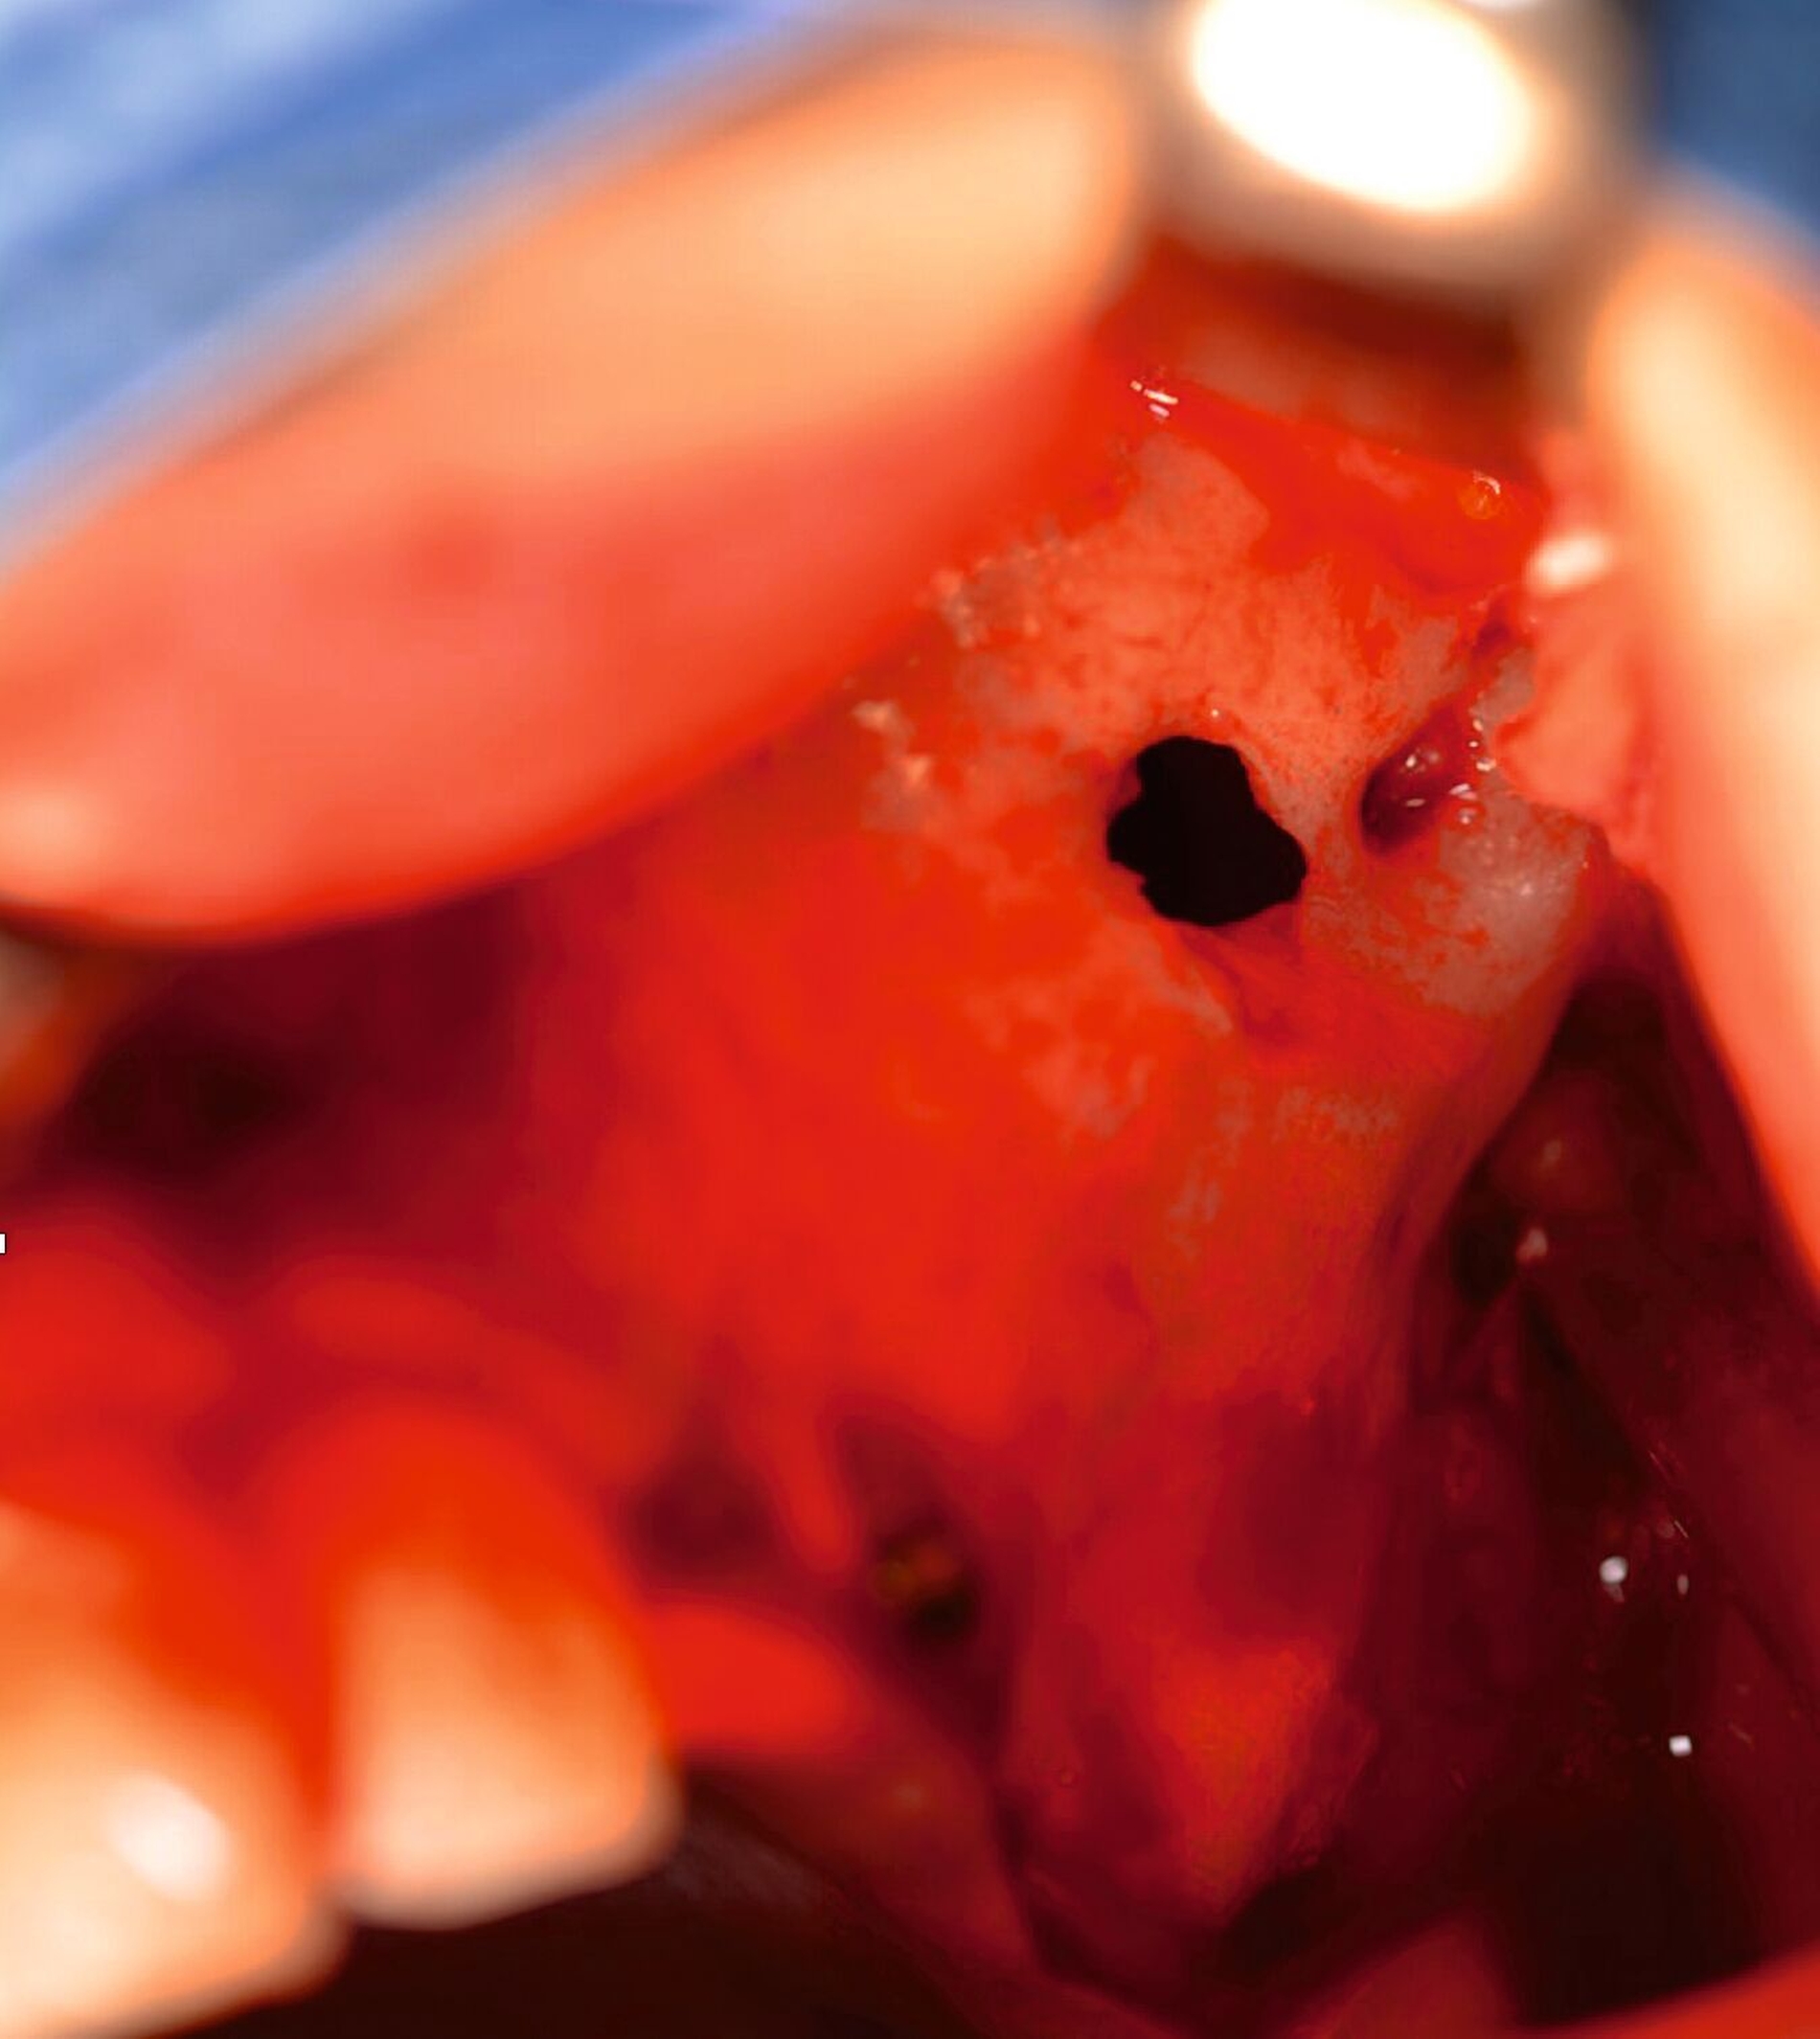

Intraoperativ zeigte sich eine reizlose intakte Kieferhöhlenvorderwand mit Osteosyntheseschrauben ohne Anhalt für Lockerung oder Superinfektion (Abbildung 6). Die Schrauben wurden komplikationslos vollständig entfernt; die anteriore Kieferhöhlenwand zeigte sich als gut verheilt (Abbildung 7). Mittels transnasaler Endoskopie wurde über den vorhandenen Infundibulotomiedefekt eine mikrobiologische und histopathologische Probe entnommen. Klinisch zeigte sich eine Polyposa und gräulich-brauner Detritus.

Die histopathologische Befundung zeigte respiratorische Schleimhaut mit Metaplasien und invertierte Epithelverbände, die ins subepitheliale Stroma reichten. Histopathologisch entsprach der Befund einem invertierten Papillom ohne Karzinomnachweis, der Befund war in der Histologie nur anteilig erfasst. Mikrobiologisch wurde eine aerobe Mischflora nachgewiesen.